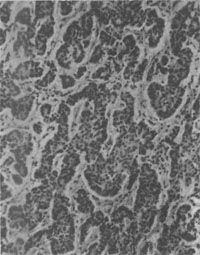

结肠类<a href=癌"/>

图10-28 结肠类

镜下见细胞较小,形态一致,为圆形或多角形,核小而规则。胞浆轻度嗜碱性,有嗜银颗粒,颗粒内含5-羟色胺。细胞形成实体状或索状胞巢,有时可见其中有假菊形团样结构(图10-28)。电镜观察可见细胞浆内有直径100~300nm的球形分泌颗粒,颗粒中有有一电子致密核心,颗粒周边有高电子密度的界膜。常限于粘膜及粘膜下层,少数可达浆膜层。发生在阑尾的类一般恶性度较低,转移率为3%。但发生在其他肠段及其他部位的类,则有约2/3为恶性者,并常转移到肝。